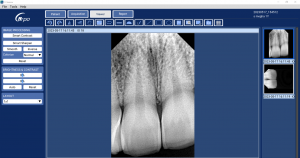

RVG technology in Dentistry has revolutionized the way dentists approach radiography, offering numerous benefits:Enhanced Image Quality

RVG provides high-resolution images, critical for accurate diagnosis and treatment planning. The clarity and detail offered surpass traditional X-ray films, allowing for better detection of dental conditions.

RVG offers instant image processing, drastically reducing the time between exposure and image analysis. This efficiency is crucial for fast-paced dental practices, aiding in quicker decision-making and treatment.

The Waldent Carpo RVG V-Sensor: A Market Leader

In the competitive world of RVG systems, the Waldent Carpo RVG V-Sensor emerges as a standout choice, especially for practices conscious of budget without compromising quality. This system is renowned for its: High-Resolution Imaging: Ensuring detailed and clear radiographic images. Durability and Ease of Use: A user-friendly system designed for the rigors of daily dental practice. Cost-Effectiveness: Priced under 1 lakh rupees, it offers high-end features without the hefty price tag, making it an attractive option for all types of dental practices.